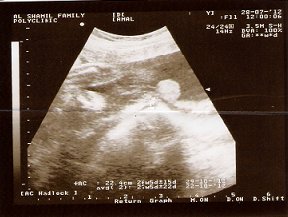

تصدقون هبلوا فيني هالمستشفيات ... فاطمه عطيه في الشامل تقول حامل بولد ... والعسكري يقول بنت .. والاحد العام يقول بنت .. واحساسي يقول ولد ... على فكره ترى عندي ولد وبنت يعني مو قضيه ..

هذي صور السونار عند فاطمه عطيه ....واحكموا ..السونار الثاني تقول ان الدائره هي (.....) للولد ..